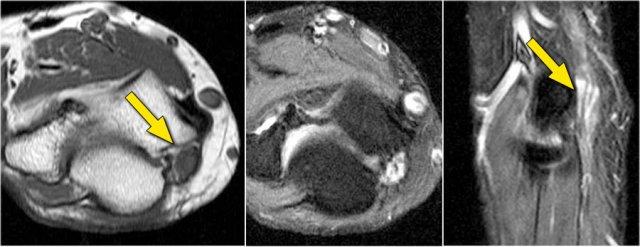

Những hình ảnh này của một nam giới 23 tuổi bị ngã chống tay khi đang trượt ván hai tuần trước.

Khi khám lâm sàng, ghi nhận giảm biên độ vận động khớp khuỷu và đau khi ấn dọc theo mặt ngoài.

Cấu trúc nào nằm phía sau chỏm quay trên hình ảnh cắt ngang?

Sagittal view:

- Một lần nữa, hình ảnh đặc trưng của phù tủy xương thường gặp trong trật khớp khuỷu tay ra sau với vết dập ở phía trước của chỏm xương quay (mũi tên đỏ) và ở phía sau của chỏm con xương cánh tay.

- Chỏm quay phải đã va chạm vào phần sau của chỏm con xương cánh tay.

Cấu trúc phía sau chỏm quay là dây chằng vòng.

Nó không đều và dày lên do hậu quả của trật khớp ra sau.